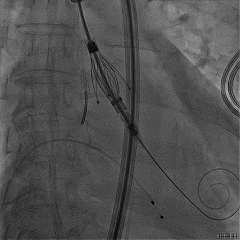

定位键解离

推送入窦形态改变不明显

无窦瓣叶脱垂影响瓣叶夹持

回撤后增加调弯夹持瓣叶

右窦中心造影确认瓣叶夹持